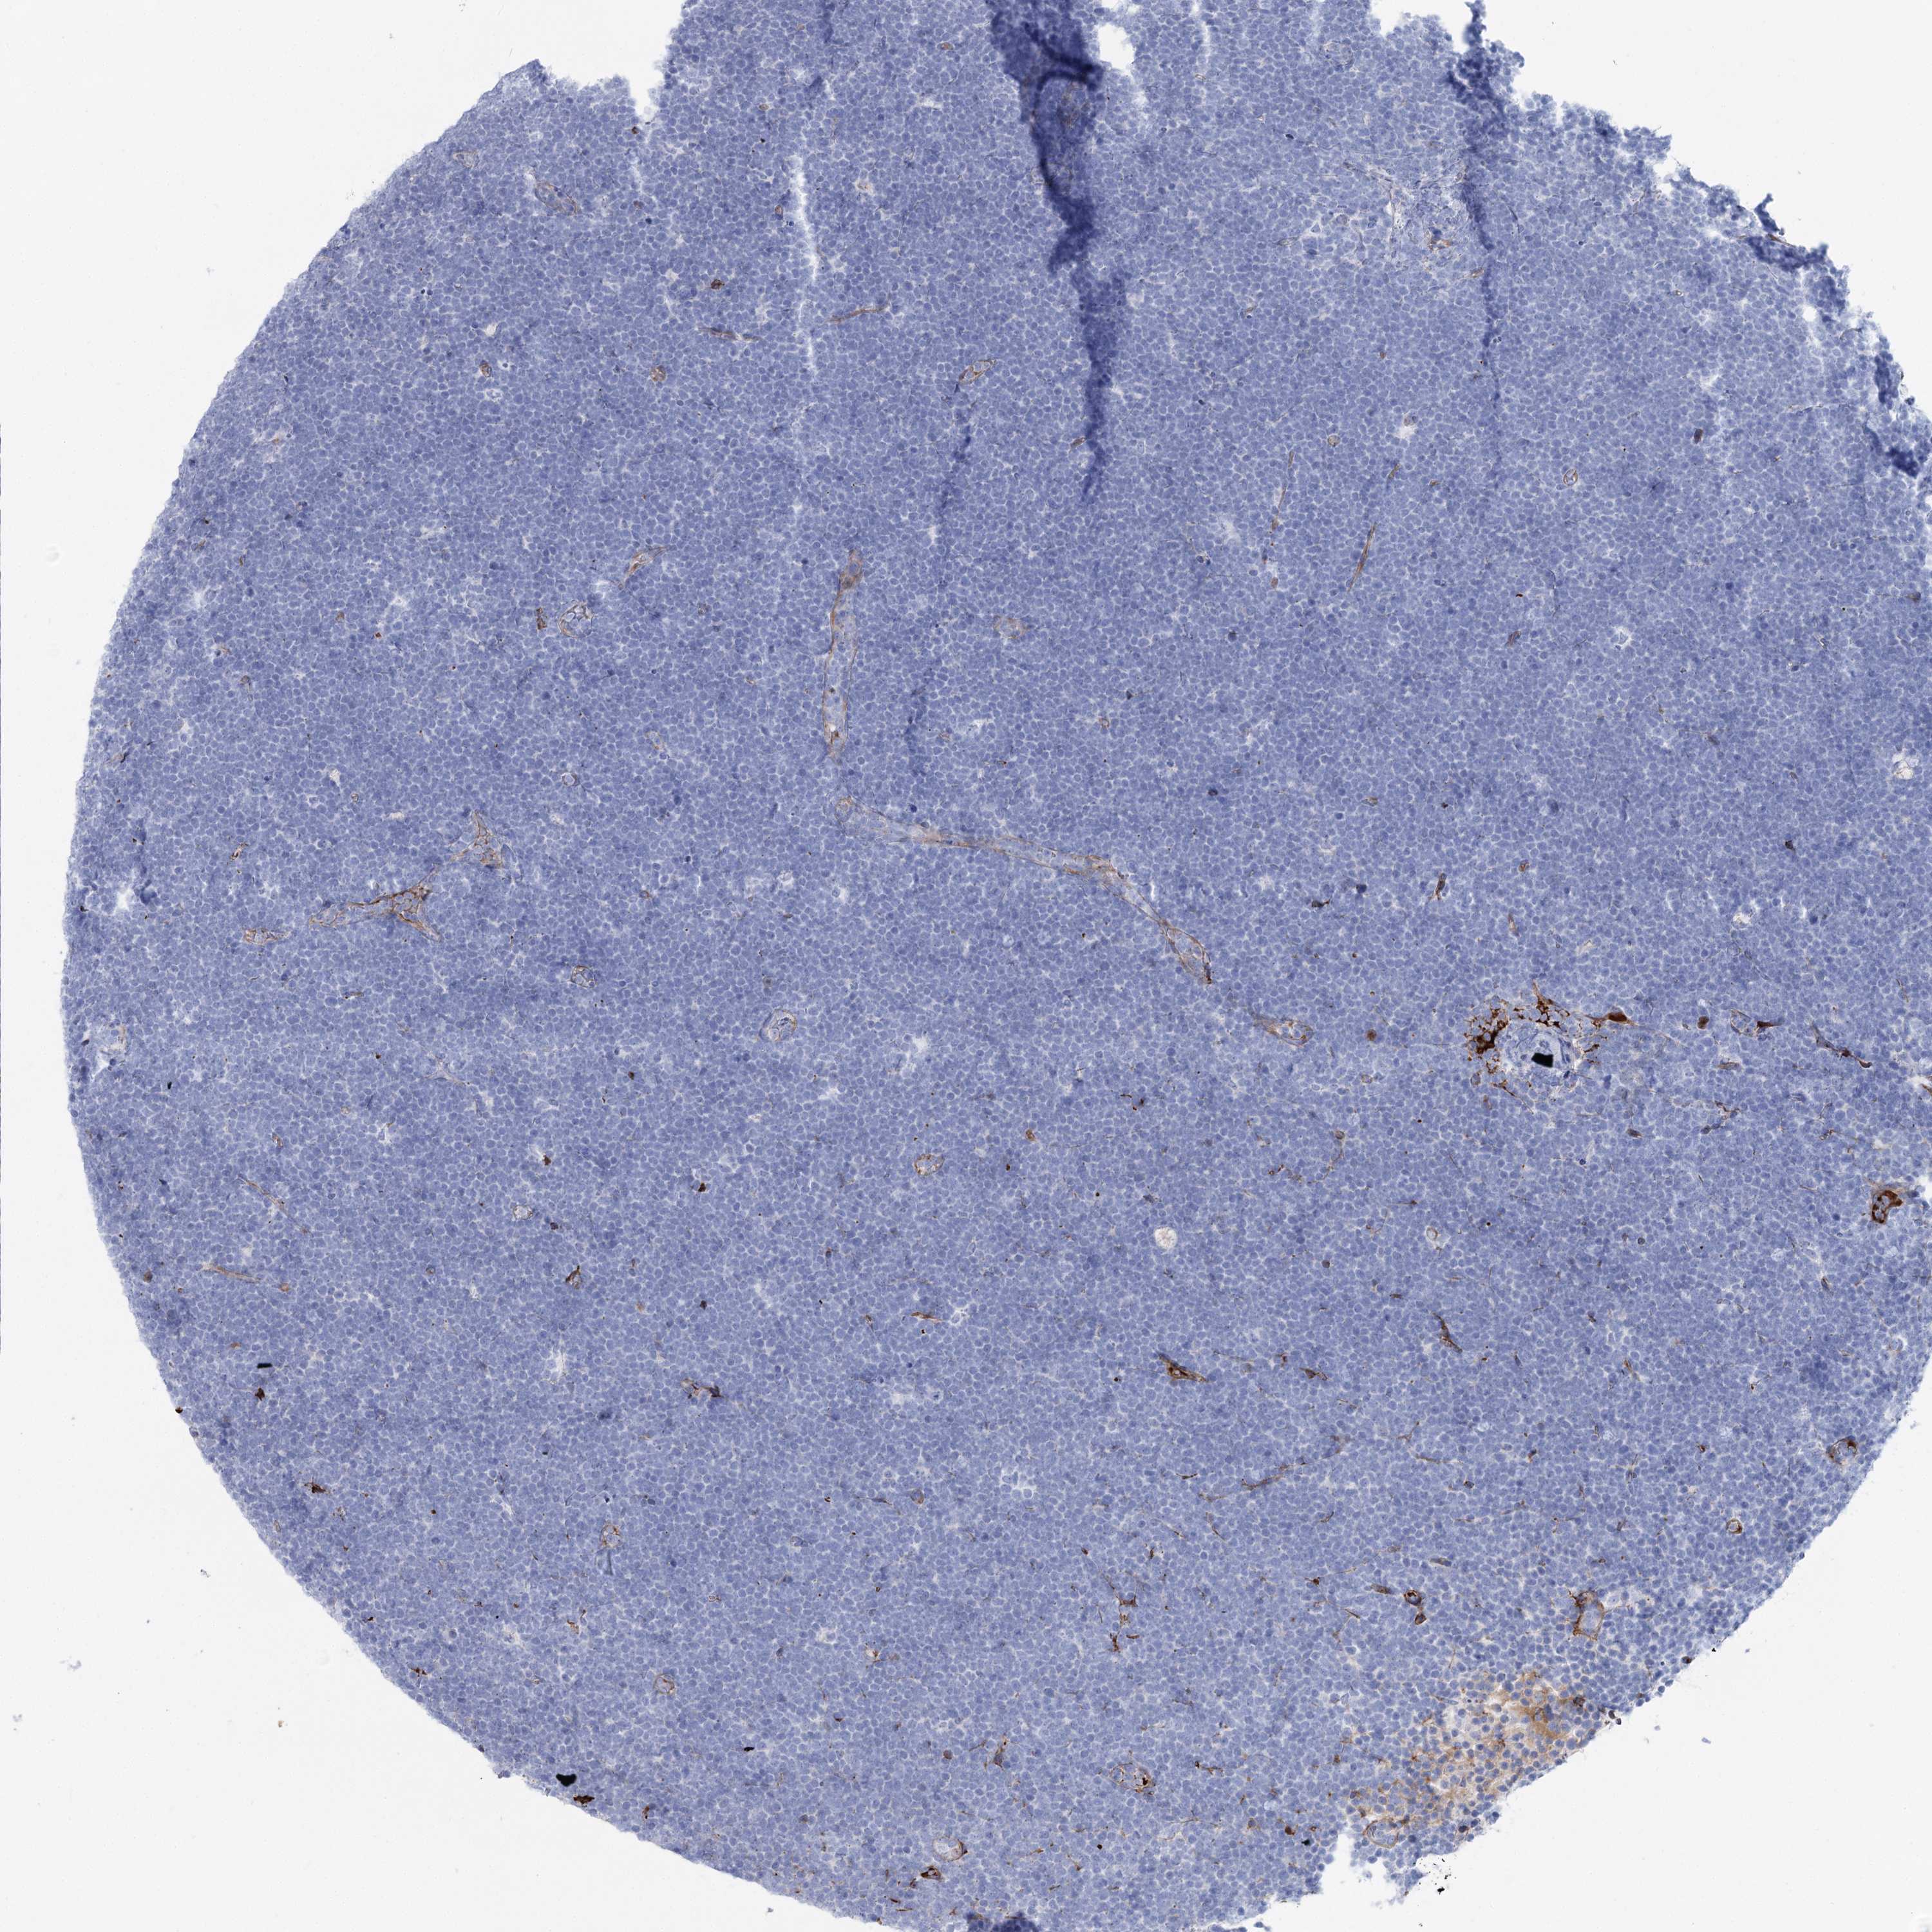

LYMPHOMA - Protein expressioni

A mouse-over function shows sample information and annotation data. Click on an image to view it in a full screen mode. Samples can be filtered based on level of antibody staining by selecting one or several of the following categories: high, medium, low and not detected. The assay and annotation is described here.

Each image is clickable and will lead to virtual microscopy that enables deeper exploration of all samples and also displays staining intensity scores, fraction scores and subcellular localization as well as patient and tissue information for each sample.

Antibody HPA036201

Hodgkin's disease, NOS

Malignant lymphoma, non-Hodgkin's type, High grade

Malignant lymphoma, non-Hodgkin's type, Low grade